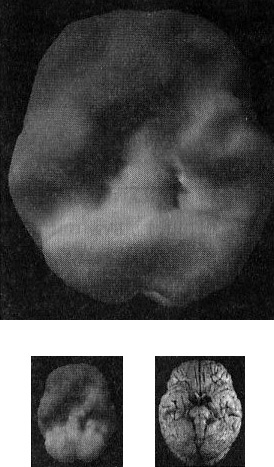

Наконец, рис. Г показывает трехмерную картину активности здорового мозга, вид снизу, а под ней находится иконка с моделью мозга в той же проекции. ![]() Помните, что трехмерные поверхностные сканы помогают увидеть малоактивные области, а трехмерные функциональные сканы помогают обнаружить гиперактивные области. Как не бывает двух одинаковых лиц, так нельзя встретить и два одинаково выглядящих мозга. С эстетической точки зрения бывают красивые и уродливые, банальные и причудливые мозги. Но всегда справедливо — и это доказали 30 000 проведенных мною сканирований, — что активность здорового мозга должна быть достаточной, полной, равномерной и симметричной. В здоровом мозге целы все важные участки, и все они работают гармонично. Возрастные вариации нормальны. Сканы мозга детей и подростков показывают большую активность, чем у взрослых. Но даже у пожилых людей мозг будет здоровым, если о нем заботились в течение жизни. Давайте взглянем на несколько примеров здорового и не очень здорового мозга. Однажды я предложил студентам стать добровольцами в исследовании функционирования мозга. Кристи, одна из вызвавшихся, воскликнула: «Вам обязательно нужно проверить мою бабушку Анну. Ей 82 года, но среди всех, кого я знаю, она одна из самых нормальных. Она вам понравится!» Бабушка согласилась, и мы провели томографию. Действительно, обнаружилось, что мозг этой пожилой женщины здоров, а ее жизнь соответствует всем критериям профилактики здоровья мозга (она не употребляла наркотики, не получала травм головы, не имела родственников первой степени с психиатрическими заболеваниями и т. д.). В течение 58 лет Анна была замужем, всегда оставаясь любящей женой, матерью и бабушкой, ее ум был острым и деятельным. Кроме того, она активно участвовала в делах местной церкви и муниципалитета. Она создала прочные и длительные отношения с родными и друзьями. Скан мозга Анны — один из самых здоровых в моей базе данных (рис. 2.5 и 2.6). Скан здорового мозга Анны, 82 года Рис. 2.5 Вид сверху Полная симметричная активность ![]() Рис. 2.6 Вид снизу Полная симметричная активность ![]() Двадцатилетний Брюс, несмотря на молодость, годами злоупотреблял наркотиками: героином, марихуаной, амфетаминами, галлюциногенами, экстази и обезболивающими. Я познакомился с ним, когда снимал образовательный фильм о вреде наркотиков. Брюс не был способен завязать со своим пристрастием. Отношения с родными разладились. Он стыдился себя и своего поведения. Как вы сами можете увидеть, мозг 82-летней Анны на томограмме выглядит значительно здоровее поврежденного наркотиками мозга молодого Брюса (рис. 2.7). Поврежденный наркотиками мозг Брюса Рис. 2.7 Вид сверху Значительные повреждения ![]() В норме с возрастом мозг становится все менее активным, поэтому если очень пожилая женщина обладает значительно более здоровым мозгом, чем 20-летний парень, значит, у этого парня серьезные неприятности. Я убедился, что люди со здоровым мозгом ведут себя эффективно и всегда движутся к поставленным целям. Они прекрасные сотрудники, супруги, родители, друзья и граждане. Люди же с поврежденным мозгом с трудом бредут по жизни. Вспомните про болезнь Альцгеймера (БА): можно ли сказать, что заболевшие ею способны полноценно проявлять свою волю и личность? Вероятно, нет. У людей с БА функционал мозга значительно поврежден. От этой болезни страдала мать моей подруги Айзы Гиббонс, основавшей ряд центров поддержки для людей с БА и членов их семей. Мать Лизы из доброй, мягкой женщины превратилась в озлобленного, иррационального и агрессивного человека (рис. 2.8). Мозг пациента с болезнью Альцгеймера Рис. 2.8 Вид сверху Значительно снижена активность в задних частях мозга ![]() Гиперактивность мозга часто связана с обсессивно-компульсивным [2] и биполярным расстройствами и другими заболеваниями. 17-летняя Хитер очень много пила и не ладила с семьей. Я сделал томографию мозга ей и ее брату для телепередачи «Правда о выпивке», которая позже получила премию «Эмми». На сканах вы видите области очень высокой активности (рис. 2.9). Неудивительно, что девушка начала пить — она пыталась успокоить свой мозг. Гиперактивный мозг Хитер Рис. 2.9 Вид функциональной активности снизу Значительно снижена общая активность ![]() 45-летний Джимми обратился ко мне с посттравматическим стрессовым расстройством, вызванным пожаром. Томограмма показала множественные области повышенной активности, о которых можно было догадаться, судя по его тревожности, депрессии и страхам. Эмоциональные центры его мозга работали чересчур напряженно, и моей задачей было их успокоить (рис. 2.10). Гиперактивный мозг Джимми Рис. 2.10 Вид функциональной активности снизу Повышенная активность в глубоких областях мозга ![]() А теперь вернемся к разнице между «волевым» и «мозговым поведением». Плохо работающий мозг лишает людей силы воли и провоцирует деструктивные поступки. Люди с обсессивно-компульсивным расстройством (ОКР), синдромом Туретта (СТ) или зависимостью от наркотиков, скорее всего, стали жертвами своего мозга. Для ОКР характерны вызывающие огорчение навязчивые мысли или компульсивное поведение (непрерывная проверка дверных замков, постоянное мытье рук, следование ритуалам). Даже если человек понимает, что его мысли и поступки иррациональны, он все равно не может от них отказаться. В тяжелых случаях такие мысли и действия занимают большую часть дня. Сканы показывают, что при ОКР гиперактивна передняя часть мозга, провоцирующая навязчивые мысли (обсессия) или действия (компульсия). |